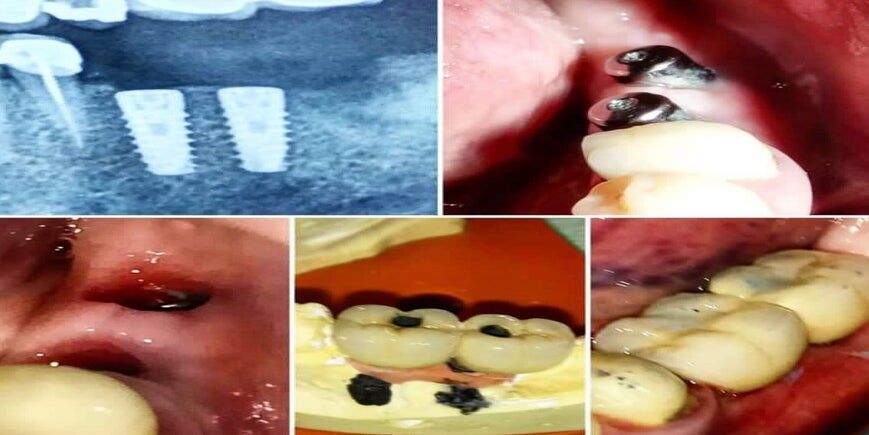

Maria K. - "Life-changing Implants"

"The dental implants I received have been life-changing. The procedure was pain-free and the results are fantastic. I couldn't be happier with the exceptional care I received."

"Τα οδοντικά εμφυτεύματα που έβαλα, μου άλλαξαν τη ζωή. Η διαδικασία ήταν ανώδυνη και τα αποτελέσματα είναι φανταστικά. Δεν θα μπορούσα να είμαι πιο χαρούμενη με την εξαιρετική φροντίδα που έλαβα."

Gallery of Smiles